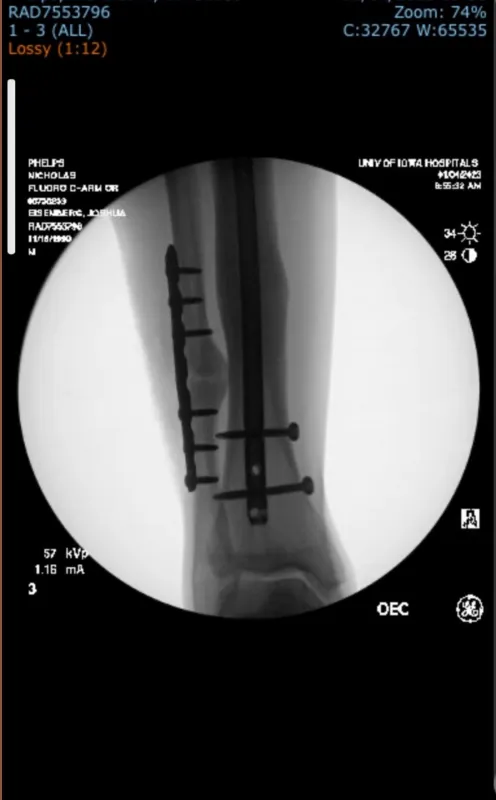

Later at University of Iowa Health Care, Phelps remembers talking to Matthew Karam, MD, an orthopedic surgeon who recommended same-day surgery to insert a titanium rod to stabilize the tibia. Both the tibia and the smaller fibula in Phelps’s right leg were broken.

Despite undergoing three surgeries in a year and a half — one to insert the rod on the tibia, another to fix the broken fibula that never healed, and the last to remove screws — Phelps was able to play football, at Iowa and then at Idaho State University during grad school. In February 2025, he completed the Mesa Marathon in Arizona.